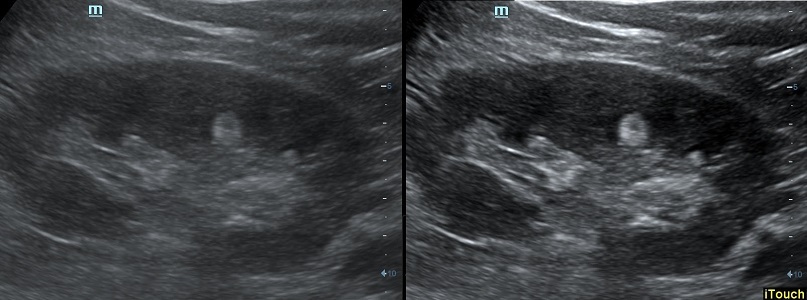

iTouch™(автоматическая оптимизация изображения)

Позволяет M7 Premium выполнять мгновенную автоматическую оптимизацию изображения в режимах В, при цветном и импульсно-волновом допплере (PW) нажатием одной клавиши.